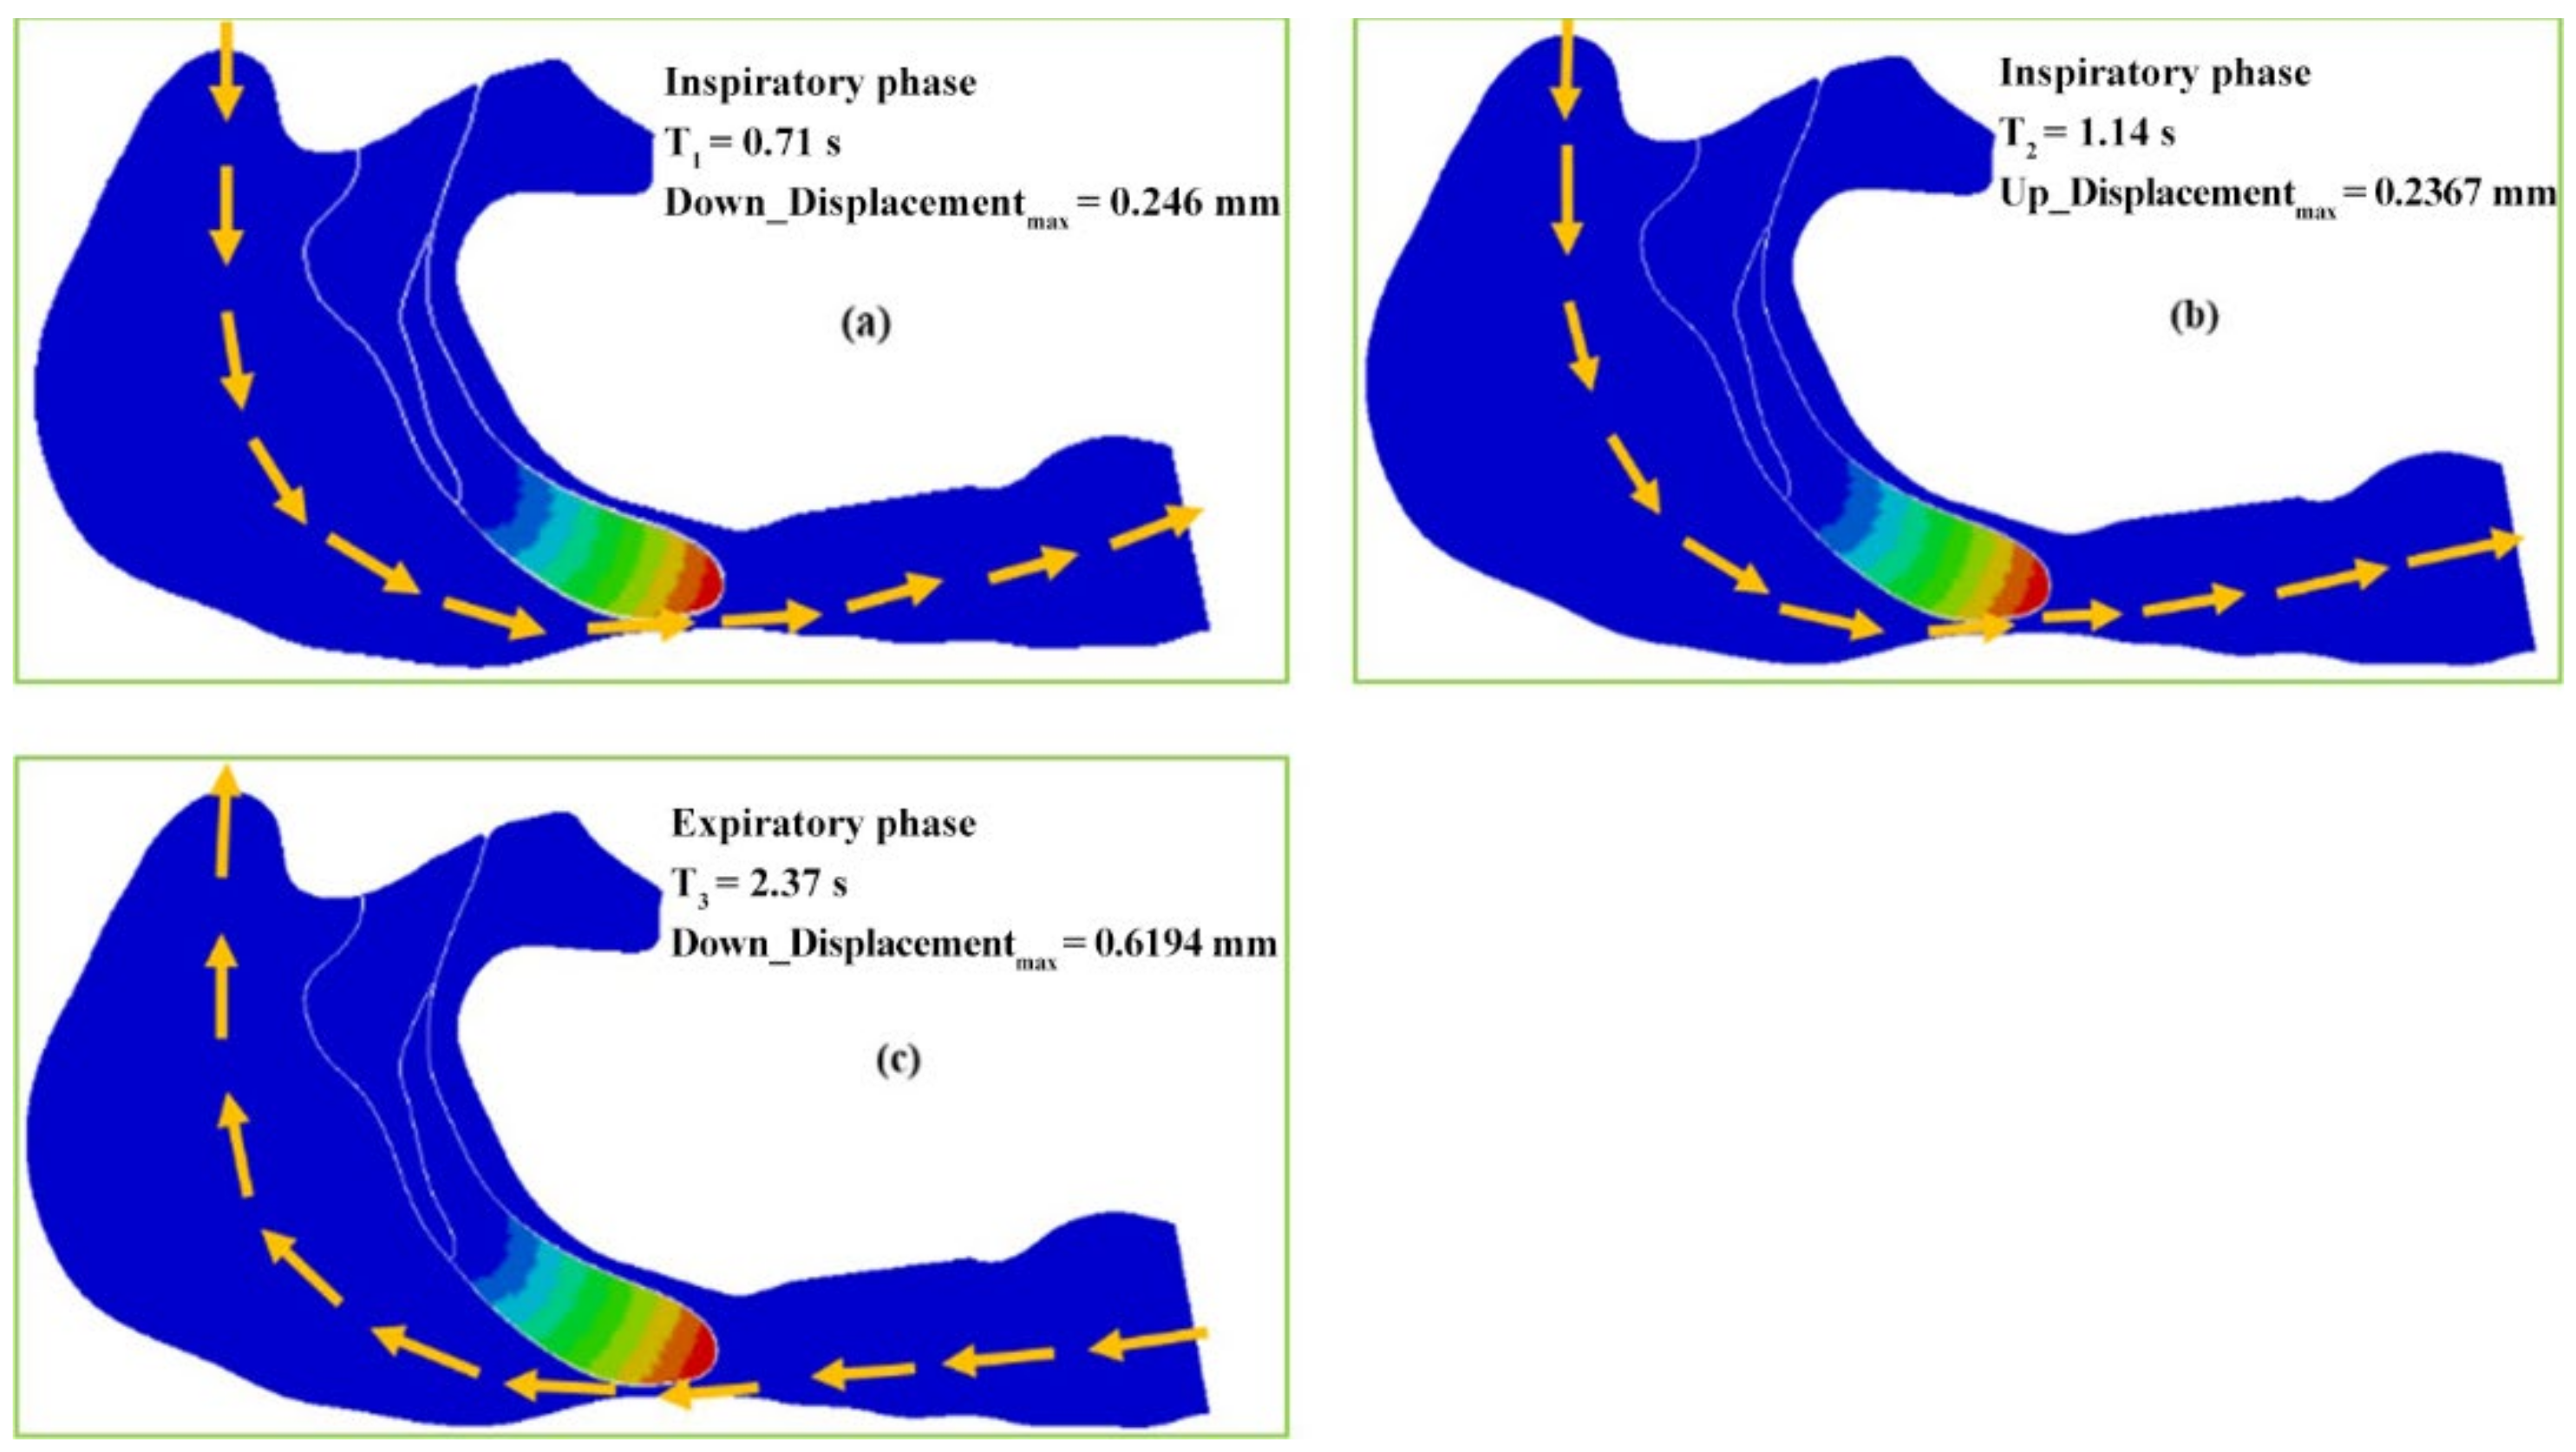

2.2.1. One-Way Valve Structure of the Soft Palate

3.1. One-Way Valve Effect of Soft Palate

- The soft palate in pharyngeal cavity would exerts a one-way valve effect and collapses in the exhalation phase if the patient sleeps in the supine position, regardless of eupnea or apnea.